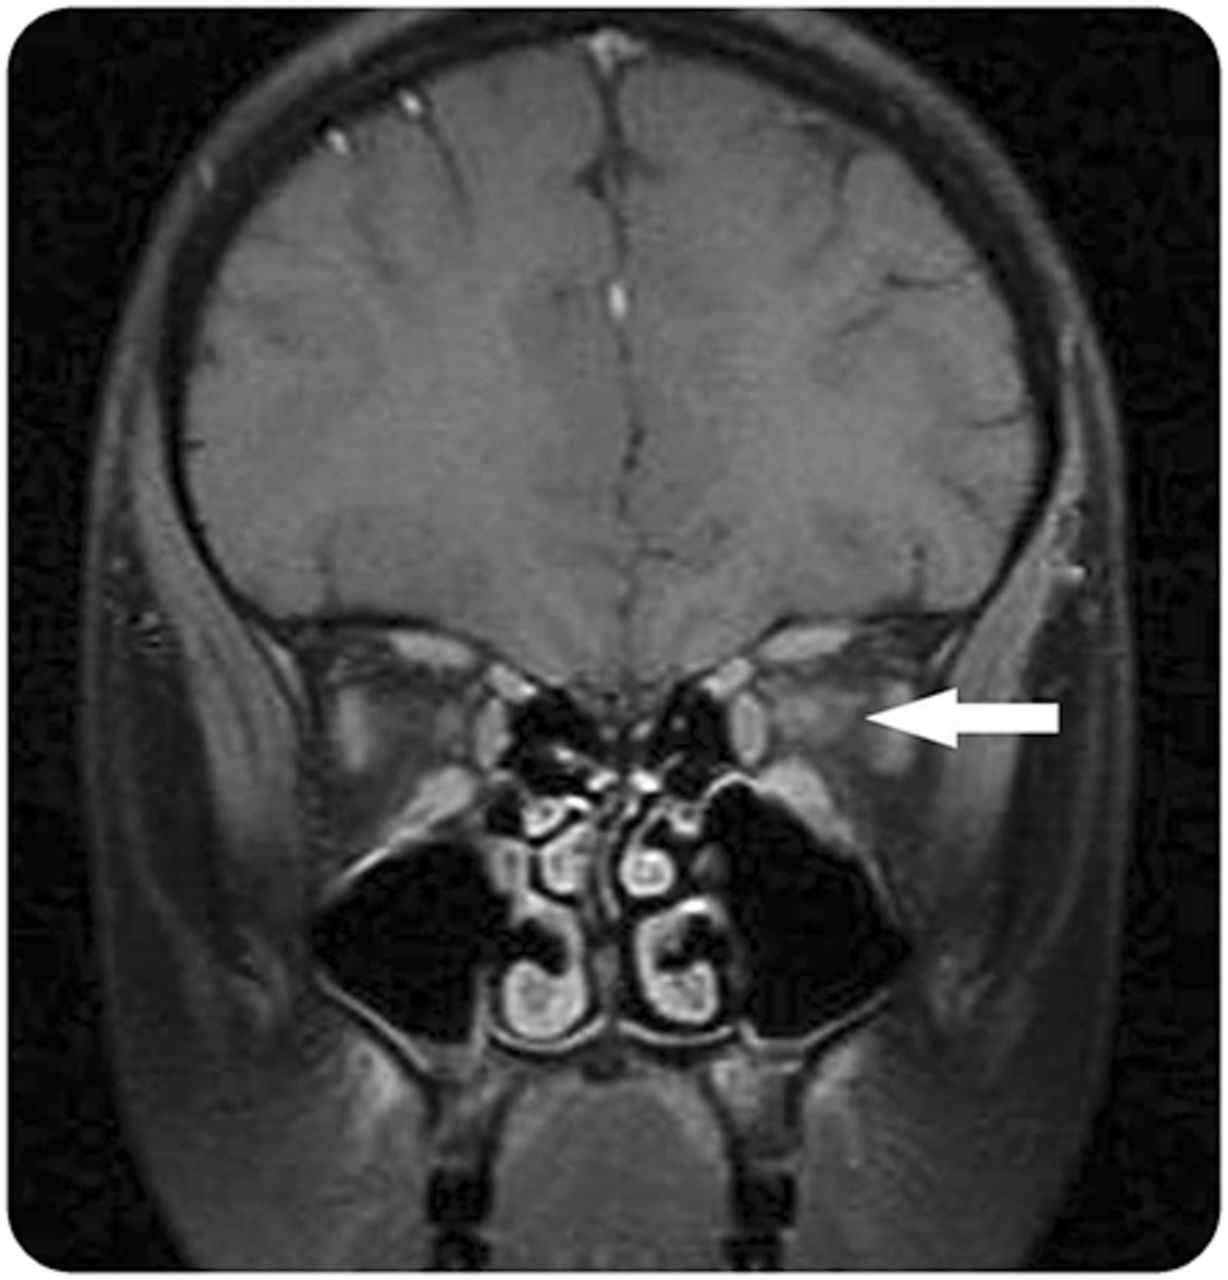

间脑的(图1一个)、下丘脑和面积postrema (图1 b)病变可能是惟一的AQP4抗体阳性病例中,有一个重要的角色在区分NMOSD中枢神经系统尤其是在其他炎症性疾病的孩子。类似于亚当,急性脑损伤往往解决重复治疗后核磁共振成像。17

12岁女孩出现棘手的呕吐,进一步发展视神经炎和纵向广泛的横向脊髓炎(积极aquaporin-4免疫球蛋白G)。(A)轴向fluid-attenuated反转恢复成像显示典型的间脑的信号变化(黑色箭头)。(B)矢状脑磁共振t2加权脑干hyperintense病变涉及背髓质(区域postrema)(白色箭头)。